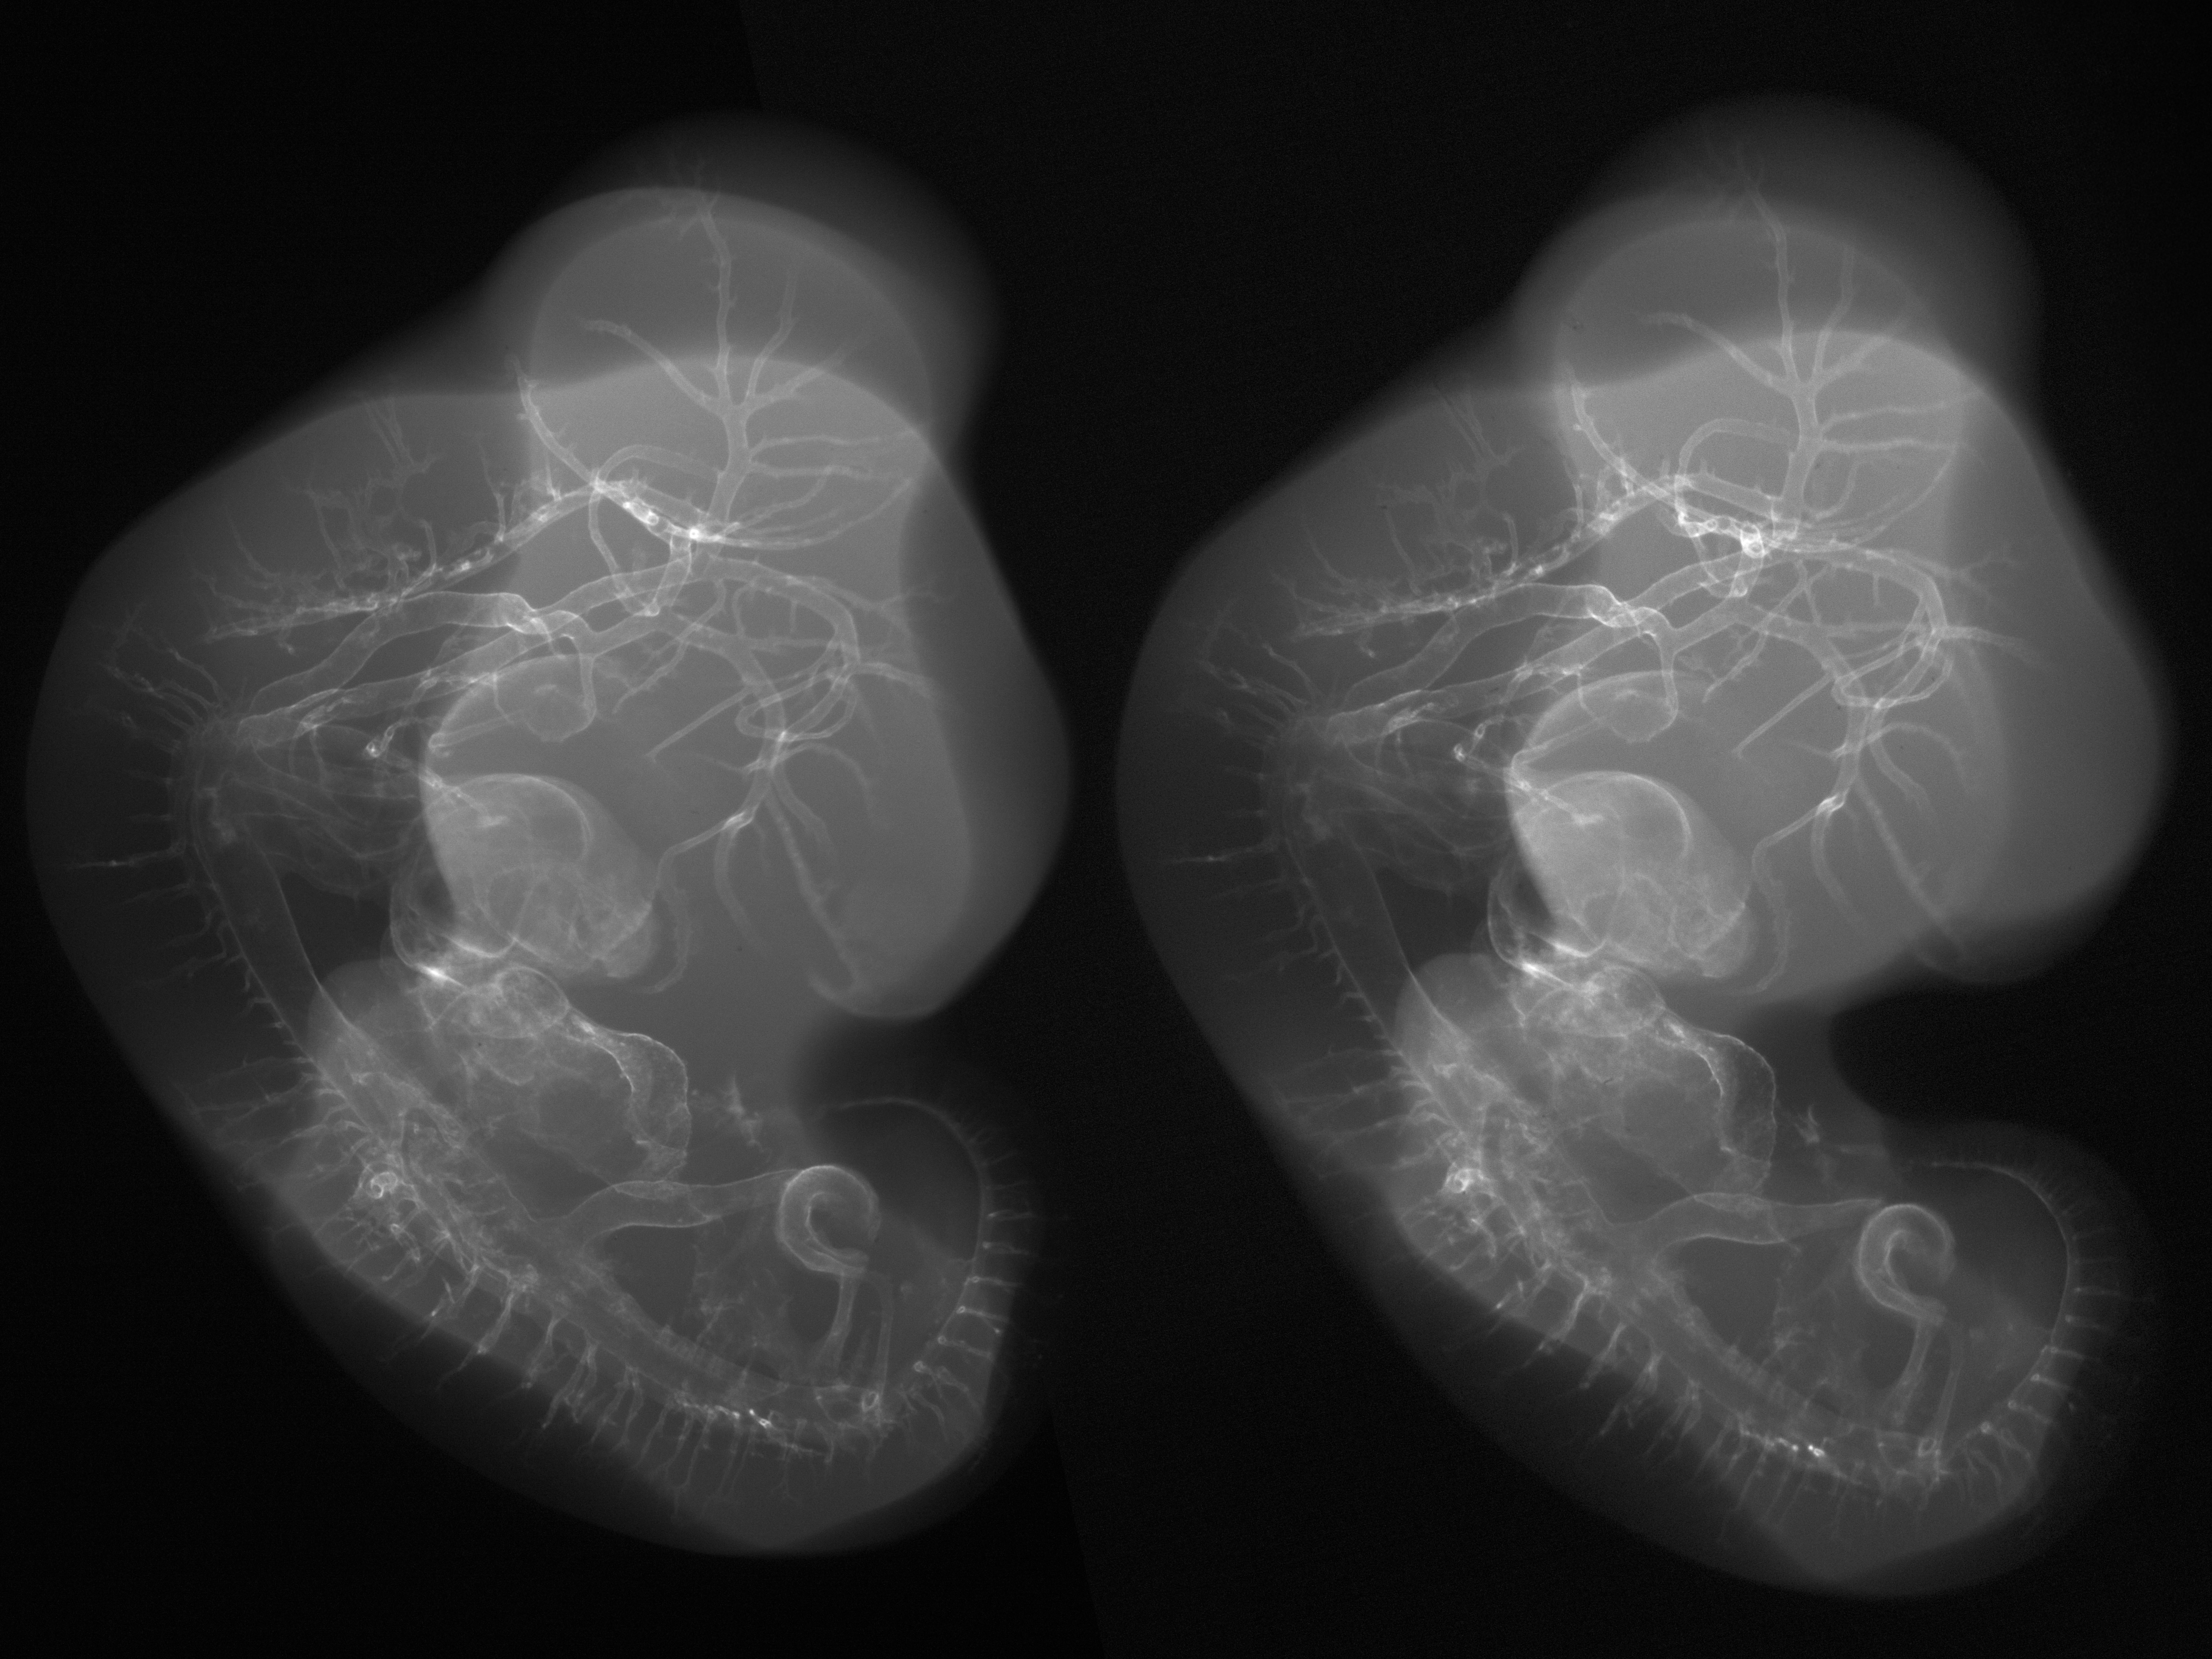

Stereo X-Ray Micrographs